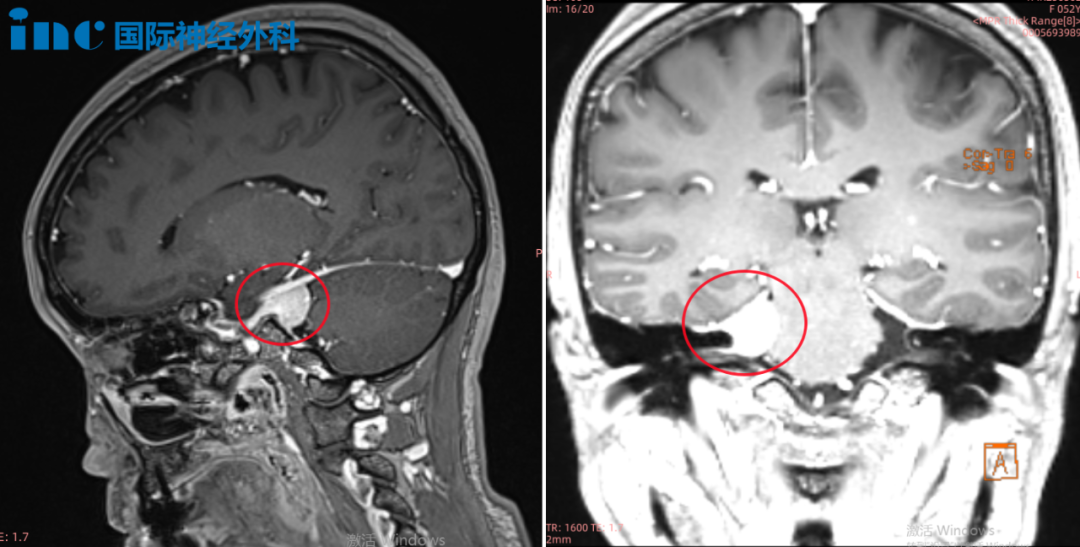

苦苦的查询之中,他们找到INC巴教授。钟女士在INC的协助下与巴教授展开了咨询,巴教授在详细诊断病情后表示,肿瘤是典型的天幕脑膜瘤(Tentorial meningioma,位于桥小脑角区,是长在大脑与小脑之间硬脑膜隔上的脑膜瘤),侵犯到右侧Meckel腔,瘤体不是很大。如果是初治时,根据肿瘤的位置,大小和患者的年龄等因素,他会建议患者手术。

钟女士2022年1月影像检查结果显示:右侧桥小脑角区占位,肿瘤侵犯到右侧Meckel腔